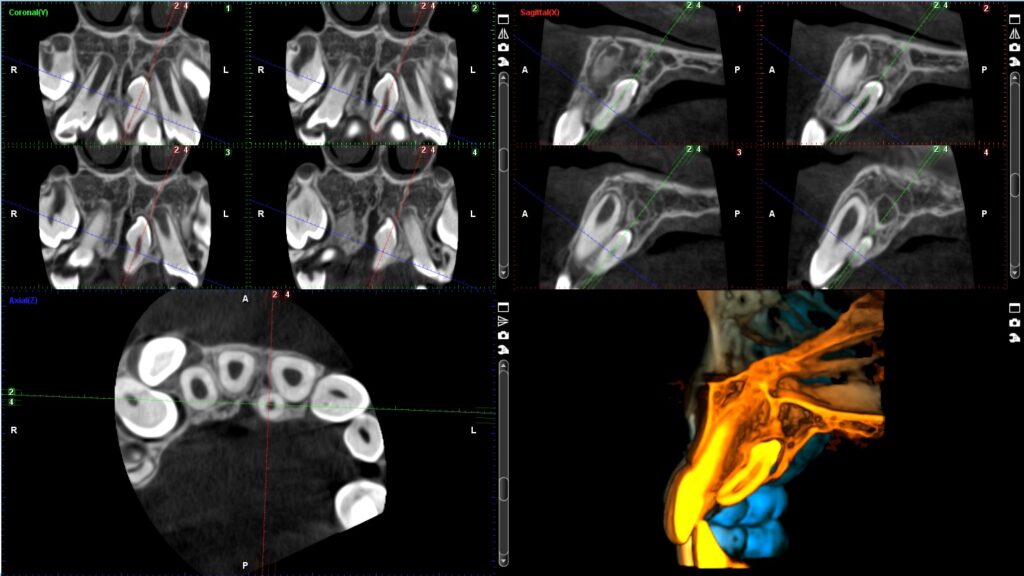

3D snimanje zuba, poznato kao konusni snimak (Cone Beam Computed Tomography – CBCT), pruža detaljan trodimenzionalni prikaz zuba, vilice i okolnih struktura. Ovaj napredni rendgenski postupak omogućava visoku preciznost u dijagnostici i planiranju tretmana, kao što su implantati, ortodontski aparati, lečenje korena i hirurške intervencije. Korišćenjem Planmeca aparata, CBCT omogućava detaljnu analizu čak i najmanjih struktura, što pomaže stomatolozima da donesu tačne i efikasne odluke za svaki specifičan slučaj.

Količina zračenja tokom 3D snimanja zavisi od veličine skenirane oblasti i veličine vokselâ (voxel size). Za aparat Planmeca ProMax 3D Mid, koji je poznat po visokoj preciznosti uz smanjeno zračenje, prosečna doza zračenja za 3D snimanje zuba je približno 10–20 mikrosiverta (µSv). Ovo je značajno niže u poređenju sa tradicionalnim CT snimanjima, koja mogu imati doze zračenja od 100–200 µSv.